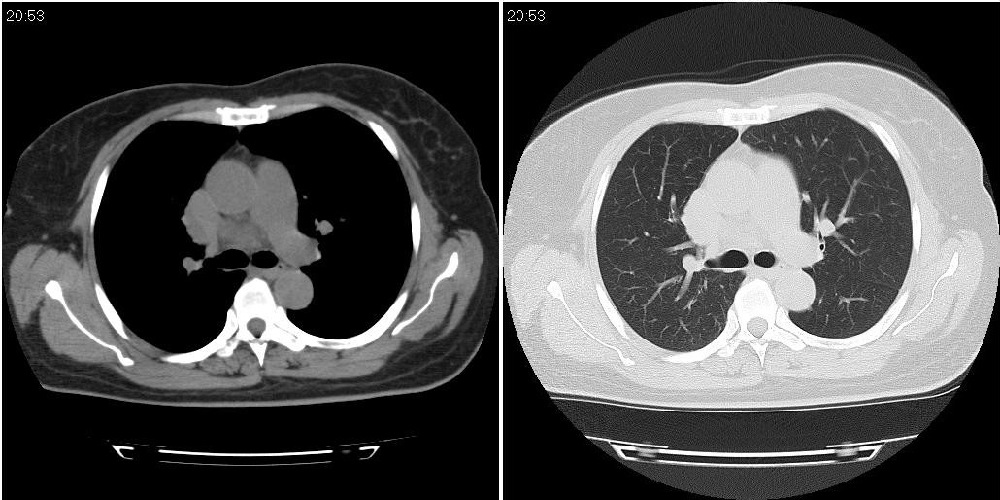

标题: CT24795:女性,47岁,右下腿静脉静脉曲张手术前体检,发现 [打印本页]

标题: CT24795:女性,47岁,右下腿静脉静脉曲张手术前体检,发现

囊性无明显占位效应:1淋巴管囊肿2畸胎瘤(其上部见小钙化)3前肠囊肿

右上纵隔囊性占位性病变;考虑淋巴管囊肿,不排除支气管囊肿。

支气管囊肿、囊性畸胎瘤、肠源性囊肿均有可能。

右上纵隔囊性占位性病变;考虑淋巴管囊肿,不排除支气管囊肿。 建议增强。

考虑淋巴管囊肿,不排除前肠囊肿。